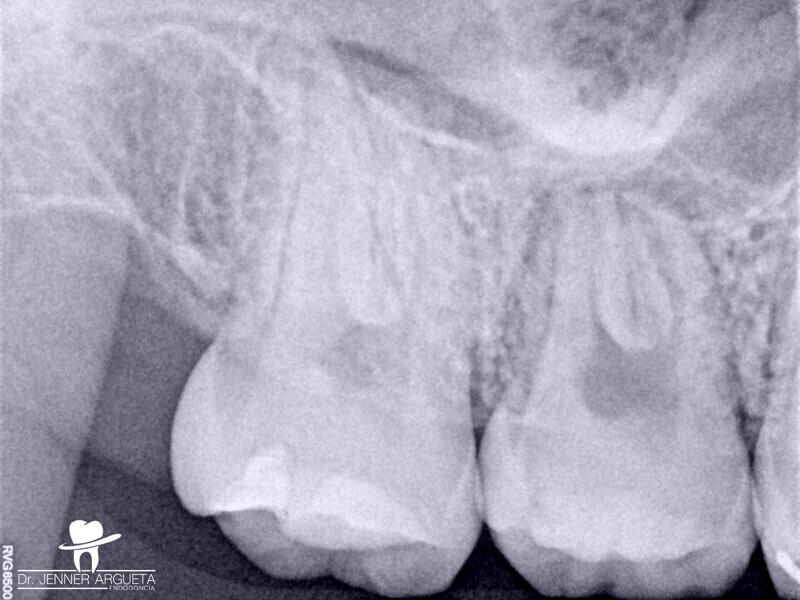

Autogenous transplantation followed by conservative root canal therapy: Three years follow-up